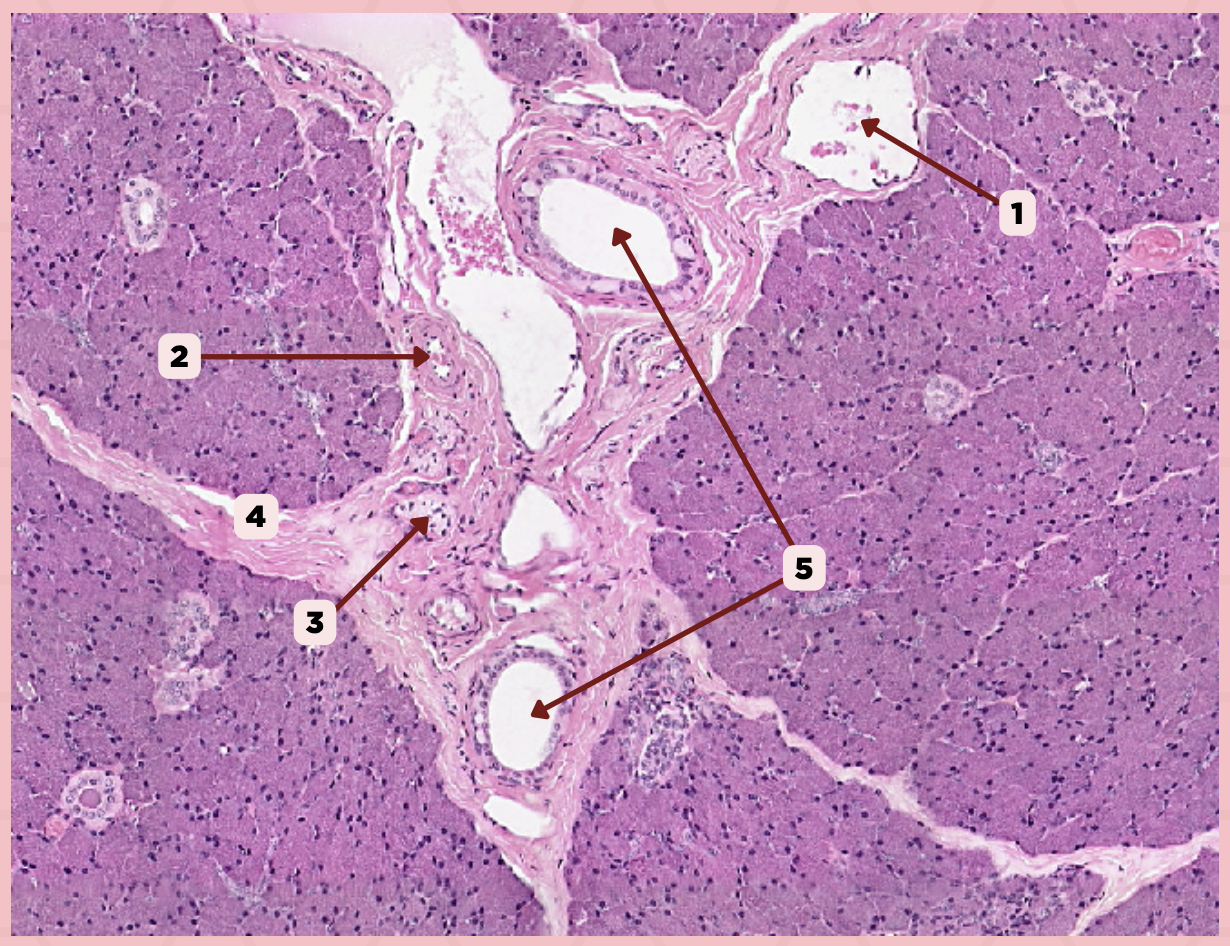

Parotid

Vein

Identify the structure labeled as 1.

Artery

Identify the structure labeled as 2.

Nerve

Identify the structure labeled as 3.

Interlobular Septa

Identify the structure labeled as 4.

Interlobular Duct

Identify the structure labeled as 5.